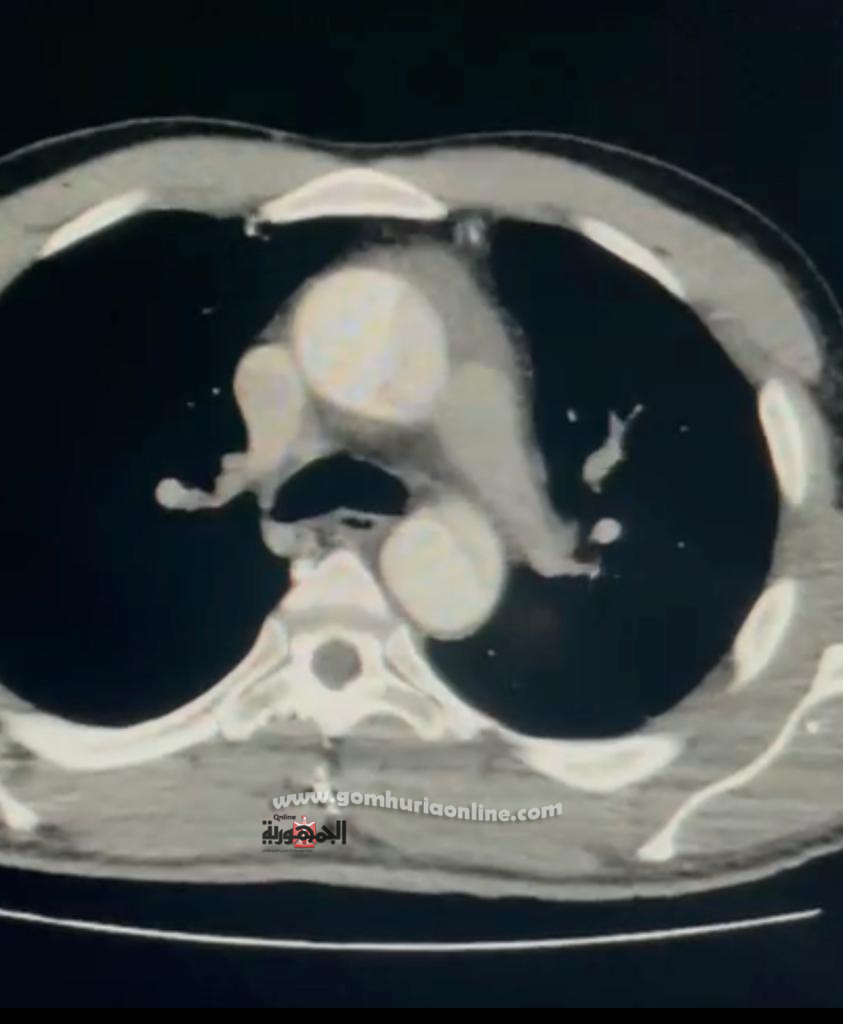

و أشار الدكتور رفيق سليمان رئيس قسم جراحة القلب و الصدر بمستشفيات جامعة المنوفية و رئيس الفريق الجراحى بأن المريض حضر إلى طوارئ المستشفيات الجامعية بشكوى من الم شديد بالصدر، و بعد عمل فحص الإيكو علي القلب تبين وجود إنشطار بالشريان الاورطى ، كما أظهرت الاشعة المقطعية انشطار بالشريان الاورطى الصاعد والمستعرض ممتدا الي كل شرايين الرقبة وشرايين الأمعاء والكلى اليسرى وشرايين الساقيين و هى من الحالات شديدة الخطورة.